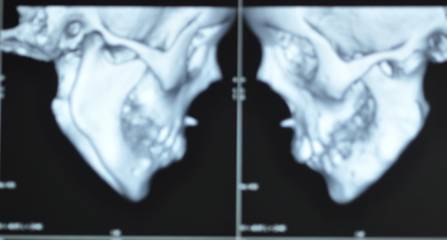

TMJ ANKYLOSIS SURGICAL MANAGEMENT, GAP ARTHROPLASTY WITH TMF FLAP